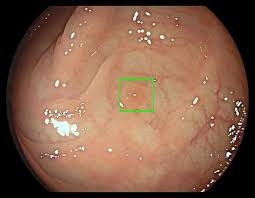

Testing yourself for colon cancer is now easier and more accurate. Colorectal cancer is the third leading cause of cancer in both men and women in the u.s.; On the contrary, it tends to show some symptoms that people may confuse with much more benign and normal problems, like the presence of stool blood. Colon cancer may begin to show symptoms and signs as the cancer grows and expands, for example, blood in the stool, bowel habit changes, abdominal pain, and fatigue. In many cases, there are no obvious symptoms of colon cancer but below given are some common symptoms that, if noticed, should be discussed with your physician. 7 signs to see your doctor. Christine brannock, rn, bs, ocn, describes how a fit test is used to detect colorectal cancer. Charlie harrington, 35, started noticing early symptoms of colon cancer in spring 2020, but for months, he thought nothing of it: Let's find out how accurate stool tests can be. One of the most common symptoms of colorectal cancer is irregular bowel movements or being unable to control your bowels. The importance of screening and early detection colorectal cancer is caused by an uncontrolled division of abnormal cells in the colon or rectum. Experiencing symptoms does not necessarily mean you have bowel cancer. Colonoscopy uses a long, flexible and slender tube attached to a video camera and monitor to view your entire colon and rectum.

Colon Cancer Causes Symptoms Treatment Options Mercy Medical Baltimore Md from embedwistia-a.akamaihd.net Monitor bowel or bladder changes. Knowing the symptoms of colorectal cancer and understanding your risks may prevent this cancer from happening to you, or help you catch it as early as possible. Colon cancer screenings can reveal precancerous polyps as well as to detect colon cancer in its early stages when symptoms are unlikely to be present. Testing yourself for colon cancer is now easier and more accurate. If your signs and symptoms indicate that you could have colon cancer, your doctor may recommend one or more tests and procedures, including: 7 signs to see your doctor. A sample of your stool is studied to check for problems in the digestive tract. Gfobt uses a chemical to detect heme, a component of the blood protein hemoglobin.